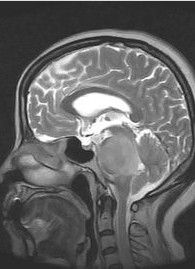

為高度惡性腫瘤,好發於2-10歲的兒童,最少者可見於幾月余小兒,大多數來源於小腦蚓部向四腦室及延髓小腦半球生長,因阻塞腦脊液循環通道,發現時多已伴有腦積水,CT及MR可發現後顱窩占位,因CT對此部位顯示不清,故推薦MR檢查。